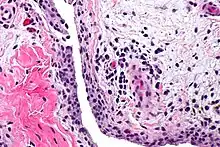

| Chronic synovitis | |

Synovitis is the medical term for inflammation of the synovial membrane. This membrane lines joints that possess cavities, known as synovial joints. The condition is usually painful, particularly when the joint is moved. The joint usually swells due to synovial fluid collection.

Synovitis may occur in association with arthritis as well as lupus, gout, and other conditions. Synovitis is more commonly found in rheumatoid arthritis than in other forms of arthritis, and can thus serve as a distinguishing factor, although it is also present in many joints affected with osteoarthritis.[1][2] In rheumatoid arthritis, the fibroblast-like synoviocytes, highly specialized mesenchymal cells found in the synovial membrane, play an active and prominent role in the synovitis.[3] Long term occurrence of synovitis can result in degeneration of the joint.